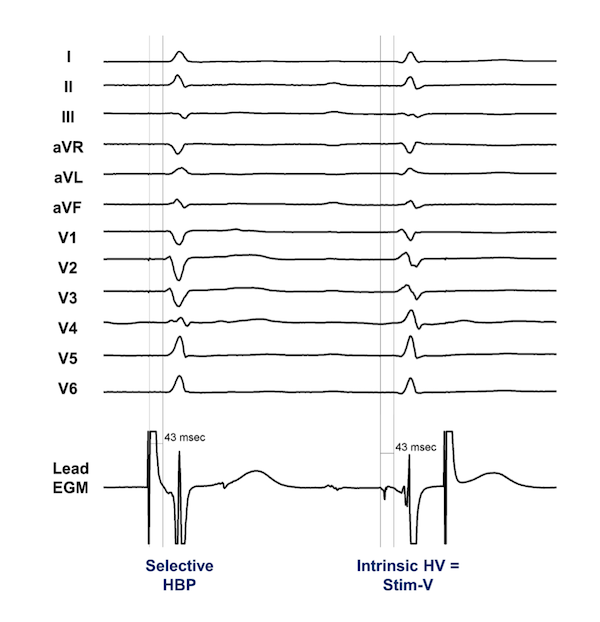

The criteria for assessing conduction system capture for patients undergoing His bundle pacing (HBP) have now been established.14 Particularly among patients with narrow QRS at baseline, the template for assessing conduction system capture is the patient’s intrinsic QRS. In patients undergoing HBP for CSP, the goal is to reproduce this QRS as closely as possible across all 12 leads of the standard surface ECG. Selective capture is present when an identical QRS or near-identical is inscribed with an isoelectric segment present between the stimulation artifact and the QRS onset in all 12 leads (Figure 1). Nonselective capture is present when there is a “pseudo-delta” or slurred upstroke beginning at the stimulation artifact in at least one lead (Figure 2). Critical in patients undergoing HBP is that output-dependent morphology (ODM) changes should be present, which allow implanters to distinguish between nonselective HBP and RV septal capture.15,16 There may be a small cohort of patients in whom ODM changes are not present with HBP, and use of pacing maneuvers may be helpful to help distinguish morphologic differences in this setting.17,18

Selective LBBP may be distinguished from LVSP since an isoelectric segment will be present in all 12 leads (Figures 3-4). Similar to HBP, nonselective LBBP will also have a right bundaloid configuration in V1 with a pseudo-delta apparent in multiple leads (Figure 5). In the case of nonselective LBBP, then, adjacent LV septal capture is present along with LCS capture. LCS capture may be assessed at implant through observation of an LBB or Purkinje potential at the lead tip during implant, although the presence of a potential does not necessarily mean it will be captured. The interval between the potential to the QRS onset should then also be similar to the width of the isoelectric segment in selective LBBP.

As an LBB potential is only variably encountered during LBBP (between 27%-80% in early work),16 approaches to ascertaining LCS capture have relied upon ECG assessment of lateral wall activation.38 Indeed, the term left bundle branch area pacing (LBBAP) has now increasingly been utilized to describe patients in whom nonselective LBBP was felt to be present based on ECG criteria, but selective LBBP could not be established. In these patients, the most commonly used criteria have examined the time from the stimulation artifact to the peak of R-wave in the lateral precordial leads (ie, V5 or V6), also called the left ventricular activation time (LVAT). Abrupt shortening of LVAT by ≥10 ms during increasing output at the time of implant and the use of a cutoff of LVAT of ≤75 ms (for non-LBBB) and LVAT of ≤85 ms (for LBBB) have been proposed.39 An important caveat here is that these LVAT references are based on a small series of patients, and there may be considerable overlap between LBBAP and LVSP over a range of LVAT measurements.19,32 The abrupt shortening of the LVAT at the time of implant during lead delivery (which occurs while traversing from the RV septum to the LV) may be the more critical criterion.

More recently, the difference between the V6-V1 interpeak interval during pacing has been proposed as a novel means to rapidly distinguish between LBBAP and LVSP.40 In patients with LBBAP, the V6-V1 interval (measured as the difference between peak of the R-wave in V6 to the time to the R’ in V1) is longer than 33 ms in patients where LCS capture is present. A note here is that there are other factors which may impact the timing and amplitude of the R-wave in V6, including cardiac rotation, degree of eccentric hypertrophy, or underlying fibrosis or scar. As such, it is unlikely that absolute cutoffs will demonstrate adequate sensitivity (although perhaps reasonable specificity) among patients with underlying cardiomyopathy.